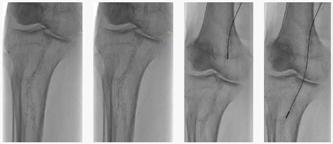

Boala arterială periferică - aterectomia rotațională în tratamentul leziunilor calcifice

Dr. Andrada Bogdan, Prof. Univ. Dr. Habil Horațiu Moldovan